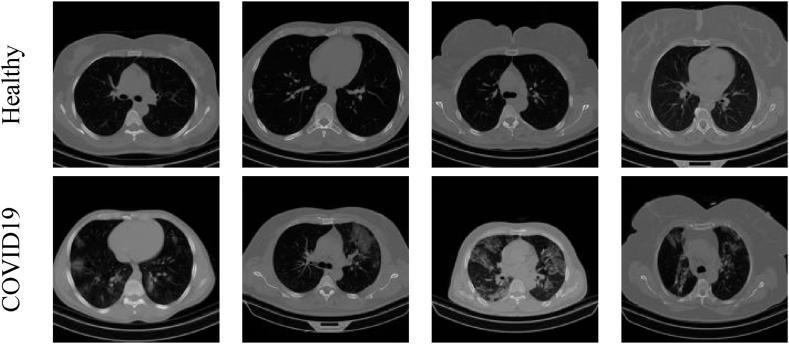

使用布朗尼蝴蝶算法优化的轻量级深度特征在肺部CT切片中检测COVID-19

COVID-19 detection in lung CT slices using Brownian-butterfly-algorithm optimized lightweight deep features.

Several deep-learning assisted disease assessment schemes (DAS) have been proposed to enhance accurate detection of COVID-19, a critical medical emergency, through the analysis of clinical data. Lung imaging, particularly from CT scans, plays a pivotal role in identifying and assessing the severity of COVID-19 infections. Existing automated methods leveraging deep learning contribute significantly to reducing the diagnostic burden associated with this process. This research aims in developing a simple DAS for COVID-19 detection using the pre-trained lightweight deep learning methods (LDMs) applied to lung CT slices. The use of LDMs contributes to a less complex yet highly accurate detection system. The key stages of the developed DAS include image collection and initial processing using Shannon's thresholding, deep-feature mining supported by LDMs, feature optimization utilizing the Brownian Butterfly Algorithm (BBA), and binary classification through three-fold cross-validation. The performance evaluation of the proposed scheme involves assessing individual, fused, and ensemble features. The investigation reveals that the developed DAS achieves a detection accuracy of 93.80% with individual features, 96% accuracy with fused features, and an impressive 99.10% accuracy with ensemble features. These outcomes affirm the effectiveness of the proposed scheme in significantly enhancing COVID-19 detection accuracy in the chosen lung CT database.

摘要